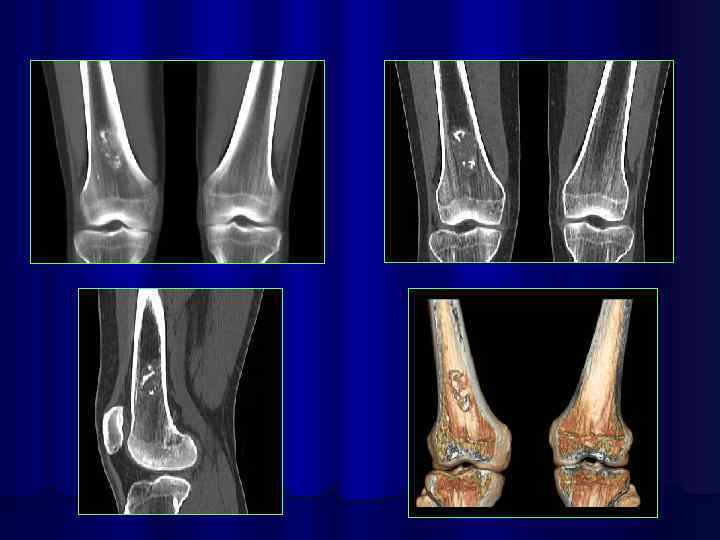

3 -d реконструкция изображений на 64 срезовом спиральном КТ